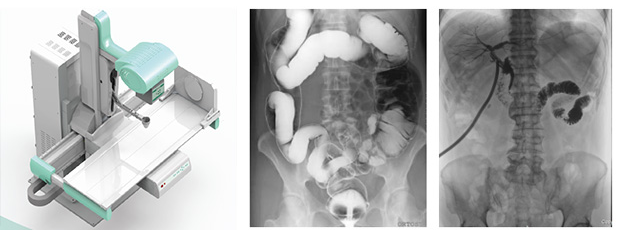

醫(yī)用DR,以其高質(zhì)量圖像和高工作效率正逐漸替代現(xiàn)在傳統(tǒng)X線攝影技術(shù), 成為當(dāng)今數(shù)字X線攝影技術(shù)的代表,它可以對(duì)于人體內(nèi)部組織進(jìn)行透視、檢查,從而快速診斷患病情況,及時(shí)給予治療。作為一種全新X線成像技術(shù),醫(yī)用DR使整個(gè)放射科特別是常規(guī)放射診斷的工作效率和經(jīng)濟(jì)效益得到明顯提高。

醫(yī)用DR是臨床應(yīng)用比較多見的放射科設(shè)備之一,其利用X射線對(duì)物體的穿透性原理,控制X射線用于對(duì)人體組織放射檢查和放射治療。如果您想購買普愛醫(yī)療的醫(yī)用DR,或了解產(chǎn)品具體參數(shù),歡迎聯(lián)系我們。